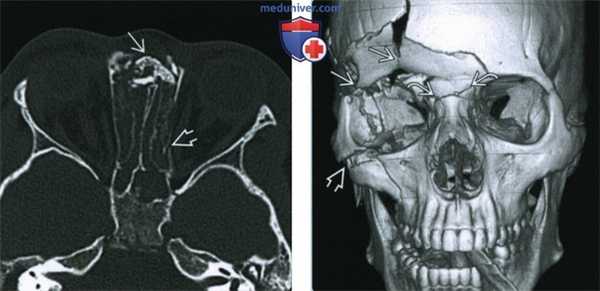

(Слева) При КТ в костном режиме в аксиальной проекции определяется типичный перелом скуло-верхнечелюстного комплекса: оскольчатый перелом левой скуловой дуги и перелом наружной стенки верхнечелюстной пазухи, вызвавший деформацию последней. Перелом передней стенки трудноразличим.

(Справа) При КТ в аксиальной проекции у этого же пациента определяется перелом и смещение латеральной стенки глазницы. Костные фрагменты пролабируют в жировую клетчатку глазницы возле наружной прямой мышцы за пределами мышечного конуса. (Слева) При КТ в аксиальной проекции визуализируется перелом правого скуло-верхнечелюстного комплекса. Наблюдается отек мягких тканей премаксиллярной области. Кроме перелома правой скуловой дуги визуализируются переломы передней и наружной стенок правой верхнечелюаной пазухи.

(Справа) На 3D реформатированном изображении определяются классические признаки перелома скуло-верхнечелюстного комплекса. Визуализируются переломы стенок левой верхнечелюстной пазухи, левой скуловой дуги и наружной стенки глазницы. У пациента также имеется травма спинки носа.

(Слева) На аксиальной КТ в костном окне определяется многооскольчатый перелом носо-глазнично-решетчатого (НГР) комплекса. Множественные мелкие фрагменты визуализируются в области внутренних углов глаз, присутствует телекантус. Определяется отек мягких тканей, эмфизема и перелом латеральной стенки глазницы.

(Справа) На более каудальной аксиальной КТ в коаном окне у этого же пациента определяется повреждение обоих носослезных протоков. В этом случае ожидаемым осложнением становится слезотечение.

(Слева) При КТ в аксиальной проекции определяются многооскольчатые переломы назо-орбито-этмоидального комплекса. В области медиальных связок век видны множественные мелкие костные отломки, отмечается телекант. Также наблюдаются отек мягких тканей, эмфизема и перелом наружной стенки глазницы.

(Справа) При КТ в аксиальной проекции (срез проходит ниже предыдущего) у этого же пациента видно, что при переломе повреждены оба носослезных канала. У таких пациентов травма осложняется слезотечением.

(Слева) При КТ в аксиальной проекции определяются оскольчатые переломы назо-орбито-этмоидального комплекса, вызвавшие западение спинки носа и перелом левой бумажной пластинки (lamina papyracea).

(Справа) При КТ (3D реконструкция) у пациента 20 лет определяются многооскольчатые переломы назо-орбито-этмоидального комплекса, глазницы и верхней челюсти.